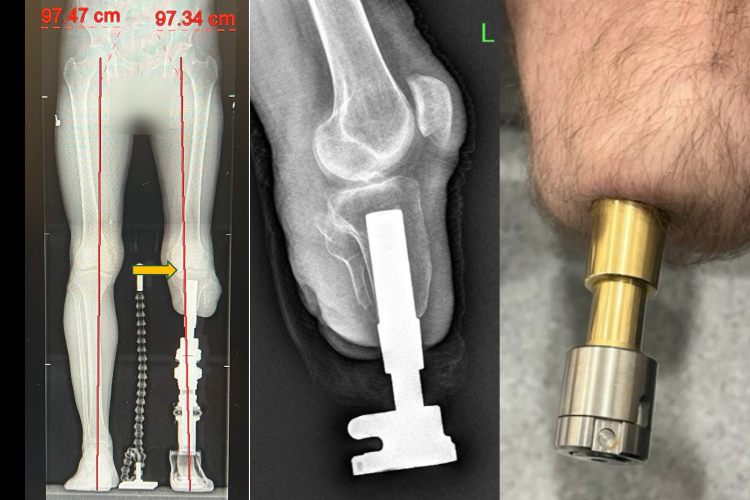

Klasik soket protezlerin yol açtığı ağrı, yara ve yürüme zorluklarına bir alternatif sunan osseointegrasyon yöntemi, amputasyon hastalarına umut veriyor. Medipol Mega Üniversite Hastanesi Ortopedi ve Travmatoloji Uzmanı Prof. Dr. Adnan Kara, Türkiye’de yeni nesil osseointegrasyon protezini ekipleriyle uygulayan ilk merkez olduklarını belirterek, "Bu yöntemle hastalar adeta kendi bacaklarıyla yürüme hissine kavuşuyor" dedi. Bu yöntemde, kemiğe yerleştirilen implant sayesinde yük doğrudan kemiğe aktarıldığından, çok daha doğal ve konforlu bir yürüyüş mümkün oluyor.

Osseointegrasyon yönteminin dünyada sayılı merkezlerde uygulandığını vurgulayan Prof. Dr. Kara, "Bu işlem sadece ortopedik cerrah ile değil, fizik tedavi uzmanı, anestezi hekimi ve deneyimli fizyoterapistlerden oluşan bir ekip ile mümkün. Multidisipliner bir yaklaşımla başarılı sonuçlar alıyoruz" diye konuştu. Osseointegrasyon protezinden kimlerinfaydalanabileceğine de değinen Prof. Dr. Kara, yöntemin en çok daha önce soket protez kullanmış ancak çeşitli sorunlar yaşamış genç ve aktif hastalara önerildiğini söyledi. "Ciltte yara oluşumu, yürüyüş sırasında ağrı, uyumsuzluk nedeniyle erken yorulma gibi sorunlarla bize gelen hastalarda bu yöntem oldukça etkili. Klasik protezlerle sadece birkaç dakika yürüyebilen hastalar, bu yeni sistemle hayatlarına tekrar karışabiliyor" dedi.

Osseointegrasyon protezlerinin getirdiği his avantajına da değinen Prof. Dr. Kara, "Bu yöntemle hastalar bir yıl içerisinde bastıkları zeminin kum, çakıl ya da düz olup olmadığını ayırt edebiliyor. Hislerin kemiğe iletildiği veriler sayesinde vücut o bacağı kendi uzvu gibi hissediyor. Bu da hastanın yürüyüşünü ve psikolojisini büyük ölçüde olumlu etkiliyor" dedi. Osseointegrasyon protezlerinin yapıldığı uzuvlar hakkında da bilgi veren Prof. Dr. Kara, yöntemin uyluk, kaval kemiği, dizüstü ve dizaltı gibi bölgelerin yanı sıra üst kol amputasyonlarında da başarıyla uygulandığını aktardı.